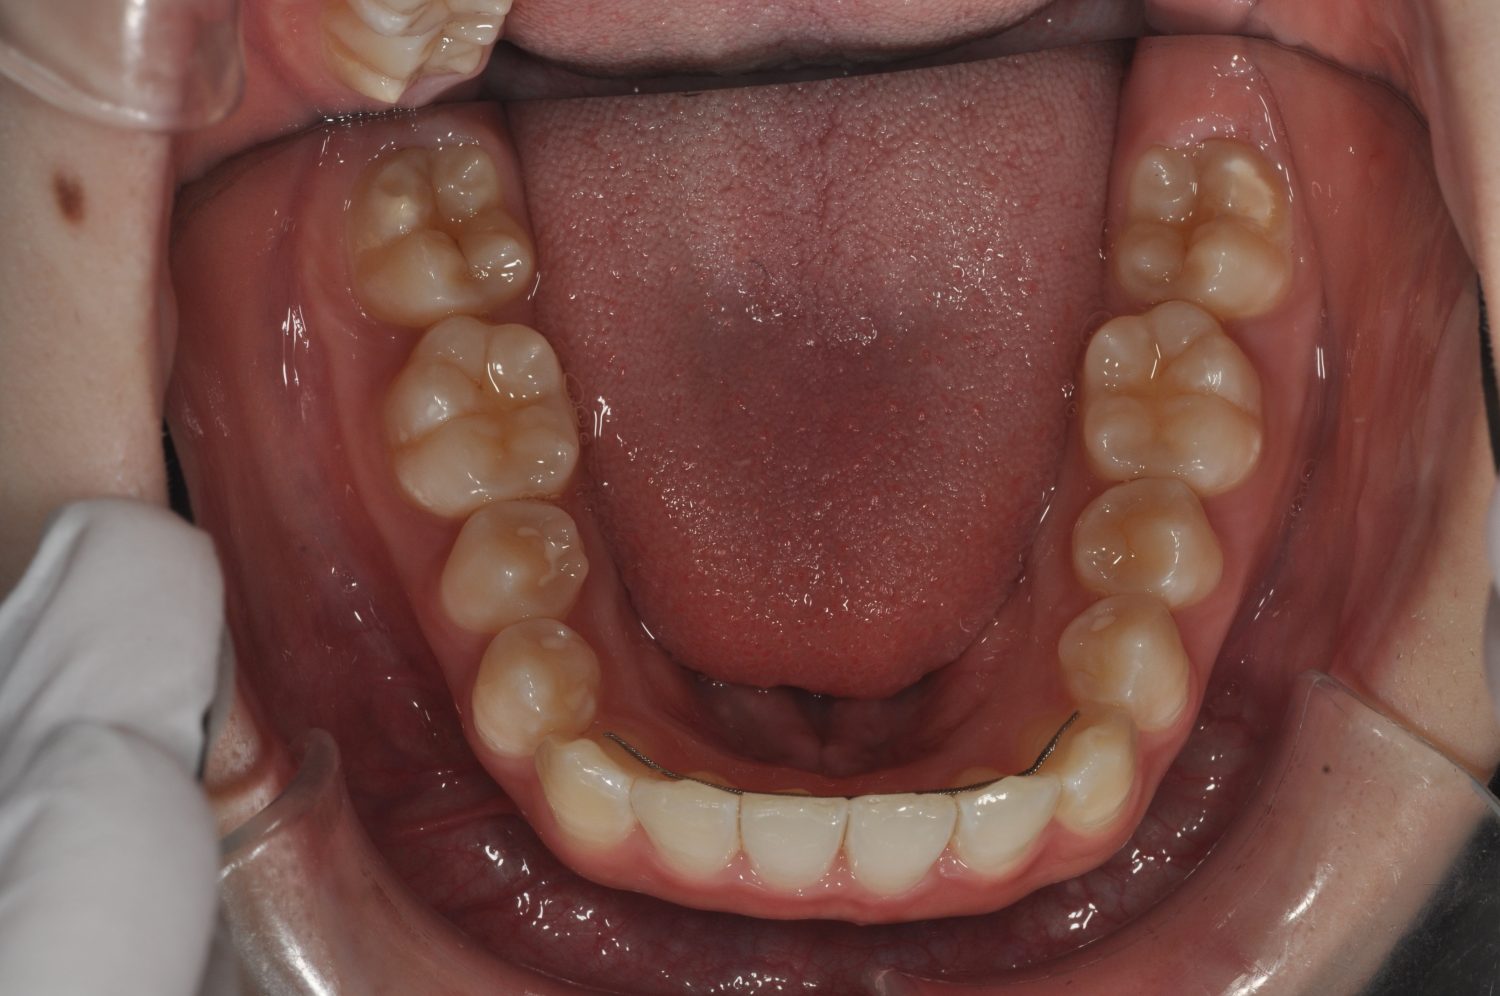

| 主訴 | 前歯部の叢生と正中の不一致 |

| 治療内容 | 軽度の叢生の改善を行うために、非抜歯でのマルチブラケット装置による治療を行った。 |

| 想定されたリスク | 矯正後に後戻りする可能性がありました。 |

Ⅰ期治療で叢生、反対咬合の改善をセクショナルアーチとMPAを使用して改善した後、成長観察を行っていました。永久歯の萌出したため、Ⅱ期治療を開始することとなった。上下顎とも骨格的に問題がなかったため、非抜歯で治療を行った。